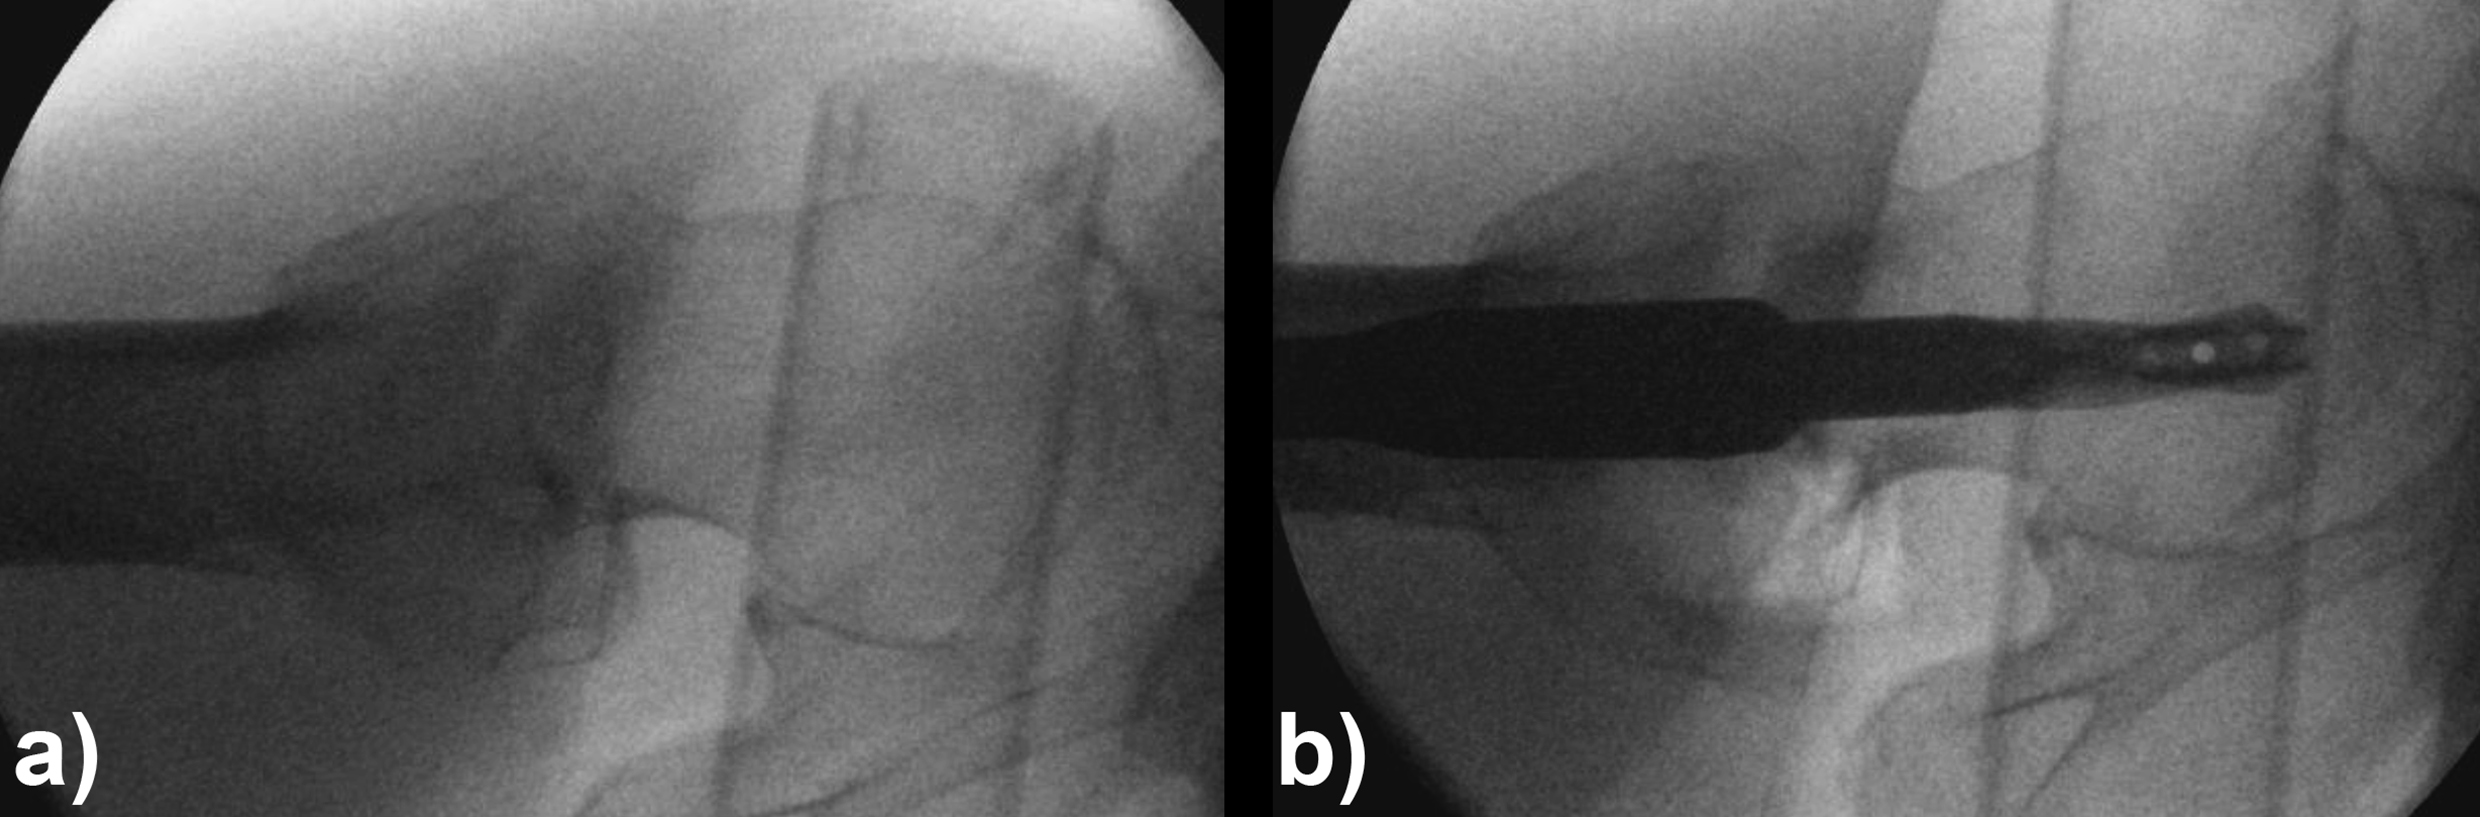

An 83-year-old female patient sustained a 31-A.2.2 fracture of the right proximal femur after a fall at home (Figs 1-2). Intraoperative and postoperative images are shown (Figs 3-5).

Case provided by Michael Blauth, Innsbruck, Austria